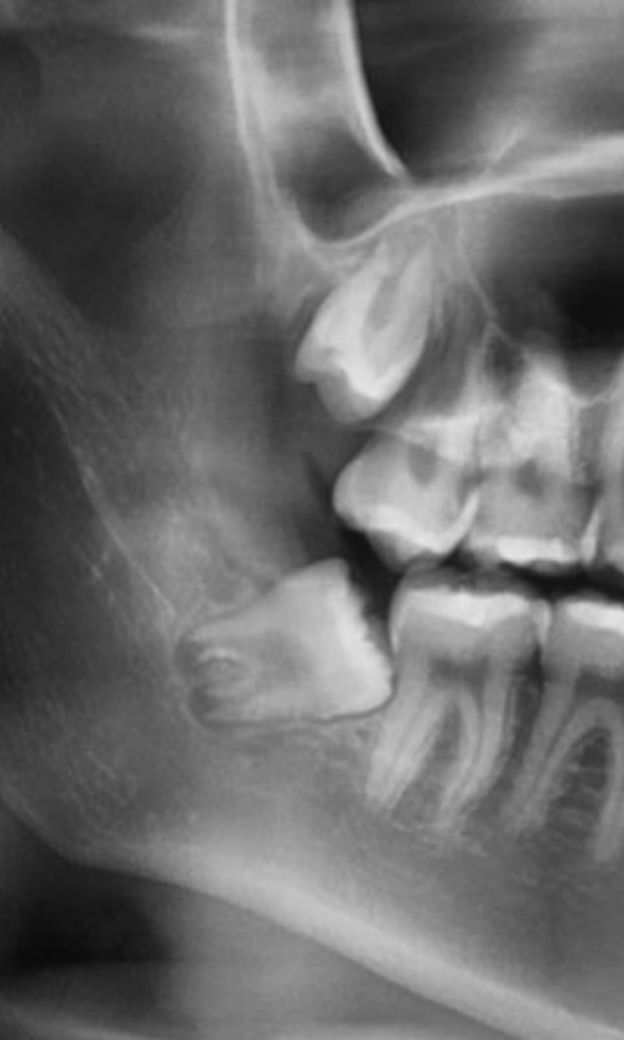

하악 사랑니가 계속 나오면서 붓고 볼살이 씹혀서 발치 하려고 생각 중인데 이 정도 치아는 발치 난이도나 발치 통증이 어느정도인가요 ㅠㅠㅠ 주변에 마취해도 아팠다는 친구들이 많아 걱정이에요 발치전에 타이레놀 먹고 가는게 도움이 되나요? 발치하는데 시간은 어느 정도 걸리나요

사진으로 봤을 경우 사랑니가 기울어져 나 있기 때문에 분리를 해서 발치를 해야 하는 난이도가 높은 발치입니다. 또한 사랑니에 뿌리가 신경관에 가깝게 위치하고 있기 때문에 발치를 하는 과정에서 신경 손상의 가능성도 있습니다. 구강외과 전문의에게 발치를 하는 것이 좋을 것으로 생각됩니다.